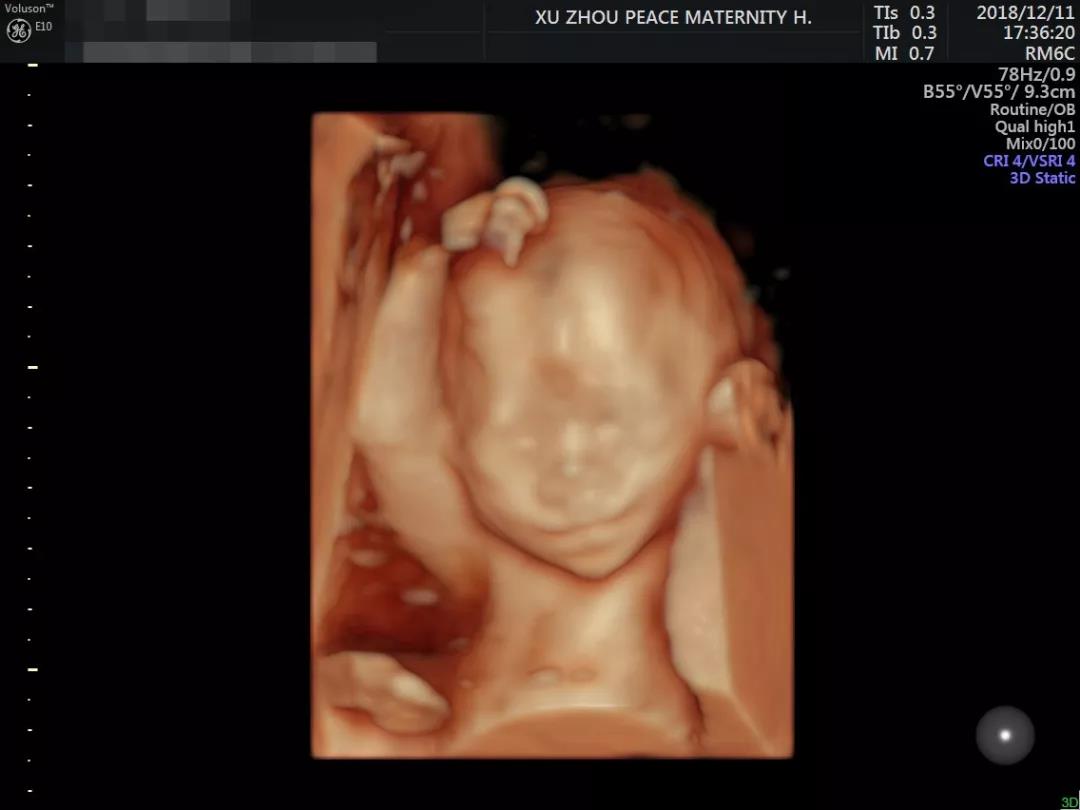

娴熟运用美国E10彩超设备

超高清的四维成像▼

耐心严谨的工作态度

以及详实细致的检查报告▼